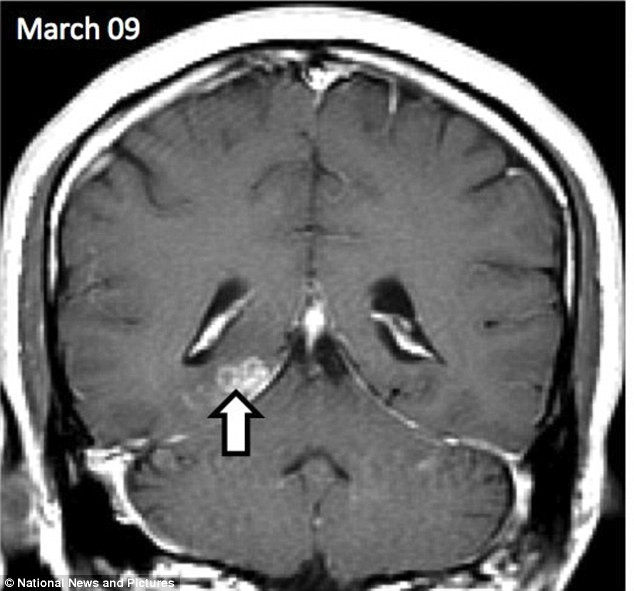

Kết quả chụp X-quang cho thấy: một con sán dài 1cm làm tổ ở bán cầu não phải đang di chuyển sang phía bán cầu não trái.

Loại sán này có tên gọi có tên gọi khoa học là Spirometra erinaceieuropaei, có nguồn gốc từ vùng Viễn Đông, là loài cực kỳ hiếm, chỉ với 300 trường hợp được ghi nhận trên toàn thế giới kể từ năm 1953.

Nó gây ra tình trạng viêm các mô trên cơ thể được gọi là sparganosis. Khi bị nhiễm sán, chúng ta sẽ rơi vào tình trạng co giật mạnh, mất trí nhớ và đau đầu nghiêm trọng.